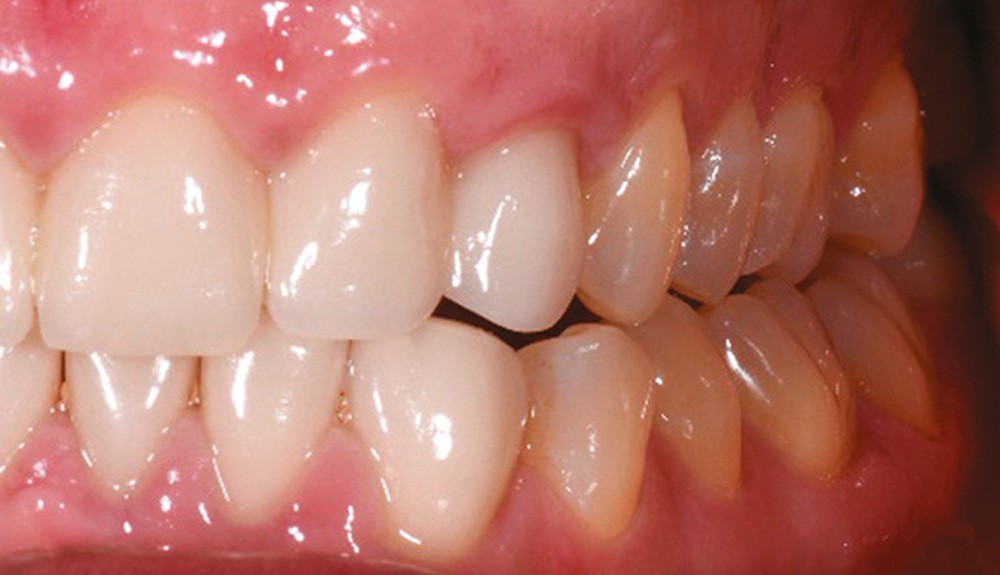

À l’examen endobuccal de première consultation (fig. 1), nous notons la présence d’un bridge maxillaire céramo-céramique sur infrastructure en zircone avec 12, 11, 21 et 22 couronnes moyens d’ancrage et 13 et 23 intermédiaires de bridge en extension. Les incisives et canines mandibulaires ont également été couronnées individuellement. Le patient nous informe que ces soins ont été réalisés pour répondre à sa demande esthétique. L’examen radiologique (fig. 2) révèle la présence de deux canines maxillaires incluses et nous montre qu’aucune dent n’a subi de traitement endodontique.